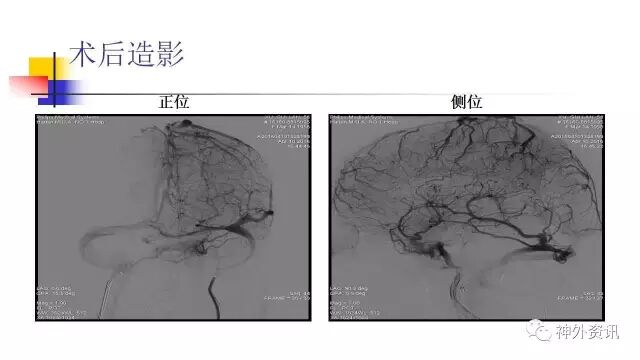

L-ICA正位动态